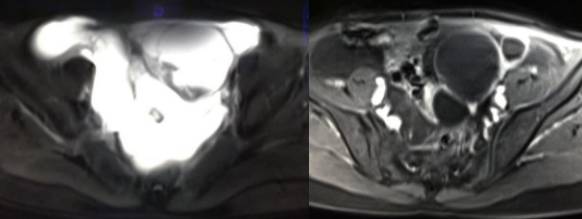

MR检查:

病理结果:黄体血肿

根据时间不同MR信号也有所不同,TIWI脂肪抑制序列可以鉴别脂肪和出血。

卵巢囊腺瘤:呈囊性或囊实性肿块,边界清楚,壁厚,有分隔或结节( 直径≤3mm) ,浆液性囊腺瘤:囊液呈T1WI 低信号,T2WI 高信号,黏液性囊腺瘤呈T1WI 高信号、T2WI 稍高信号,T2WI 信号高于水,信号较均匀,增强扫描囊壁及壁结节强化。

畸胎瘤:多呈囊性或囊实性,单房或多房状,囊内液体可有分层,实质由多胚层组织构成,MR 信号不均,肿块内见脂肪信号有利于畸胎瘤的诊断。

在鉴别卵巢畸胎瘤、出血性囊肿或巧克力囊肿时,MR 脂肪抑制T1WI 可明确肿块内高信号成分是脂肪还是出血,同时由于脂肪组织与非脂肪组织的共振频率不同,在两者交界处沿磁场频率编码方向出现化学位移伪影,但出血性囊肿与巧克力囊肿的鉴别有时较为困难。